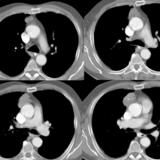

Case 8c Thymoma CT

Date: 03/27/2009

Views: 15482